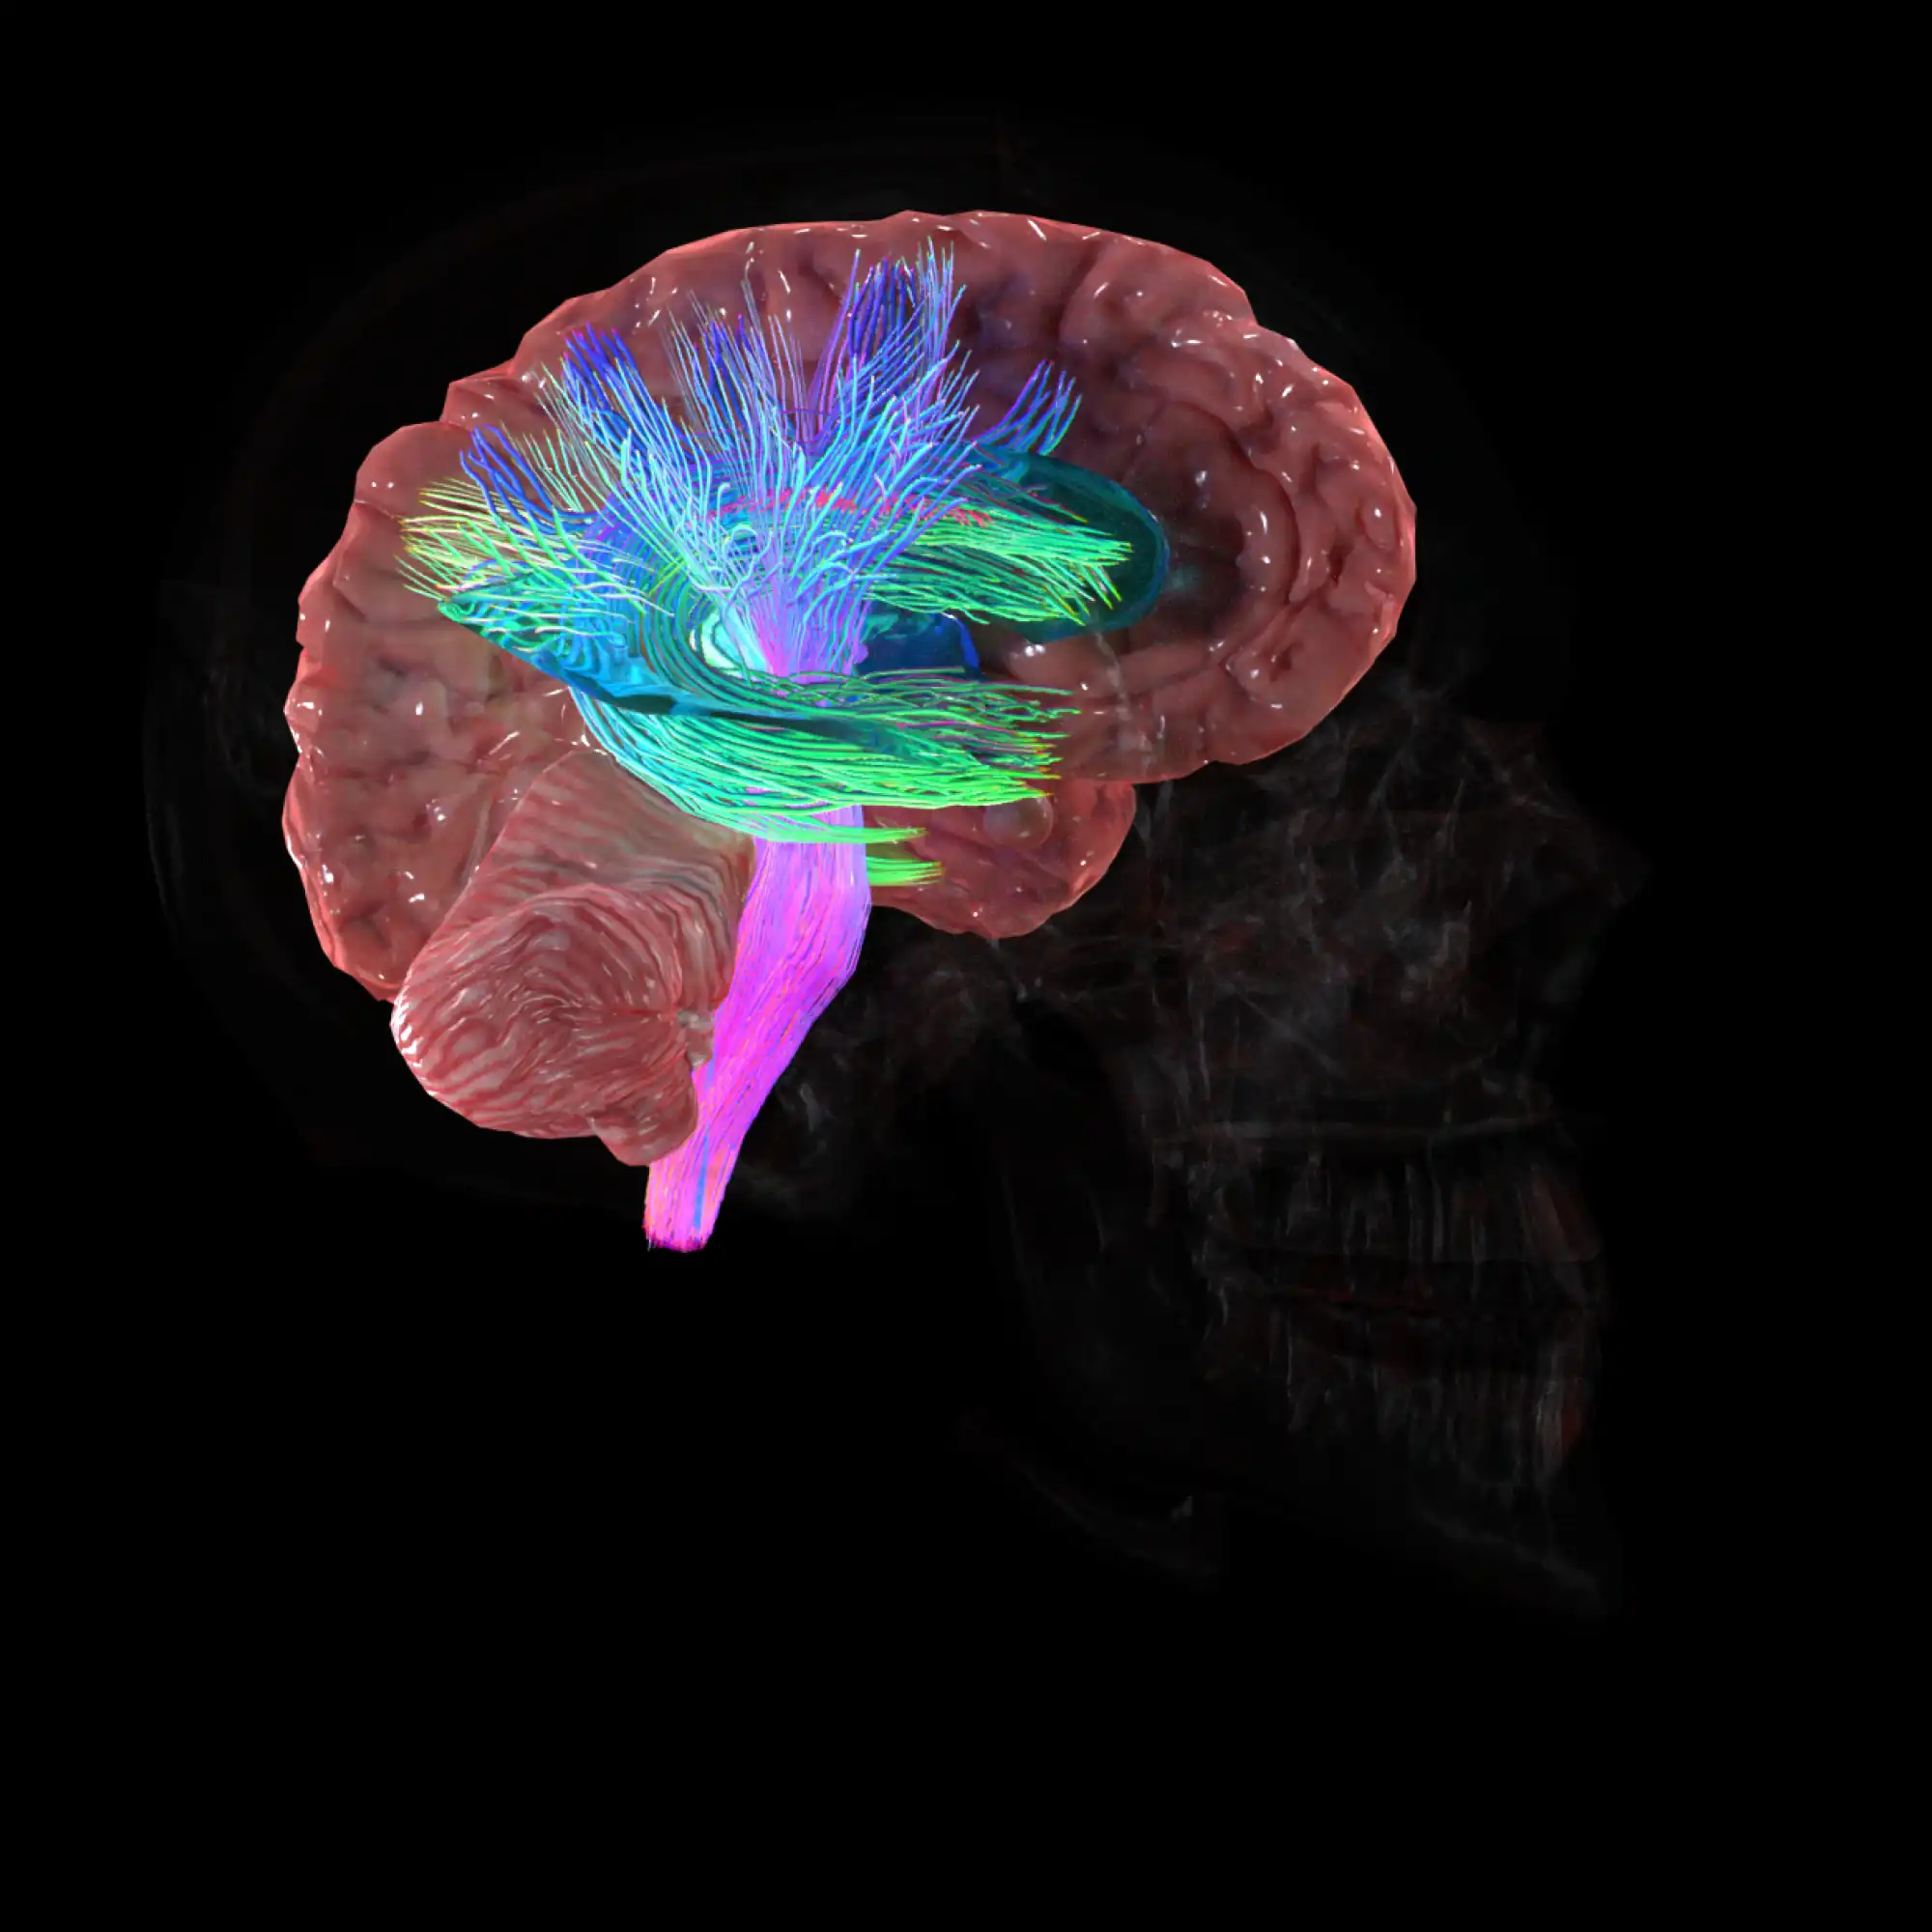

High definition models.

You will get 5,000 meticulously detailed anatomy models, designed to meet rigorous industry standards. Our in-house team has carefully crafted each 3D element, ensuring that you have access to the most accurate and highest quality models available on the market.

High definition models.

You will get 5,000 meticulously detailed anatomy models, designed to meet rigorous industry standards. Our in-house team has carefully crafted each 3D element, ensuring that you have access to the most accurate and highest quality models available on the market.

Full-body 3D learning.

Whether focusing in on the cardiovascular system, skeletal framework, nervous system or more, our immersive 3D experience brings the entire body to life. Perfect for learners at any level.